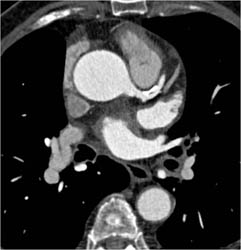

Diagnosis

Axillary Arteries